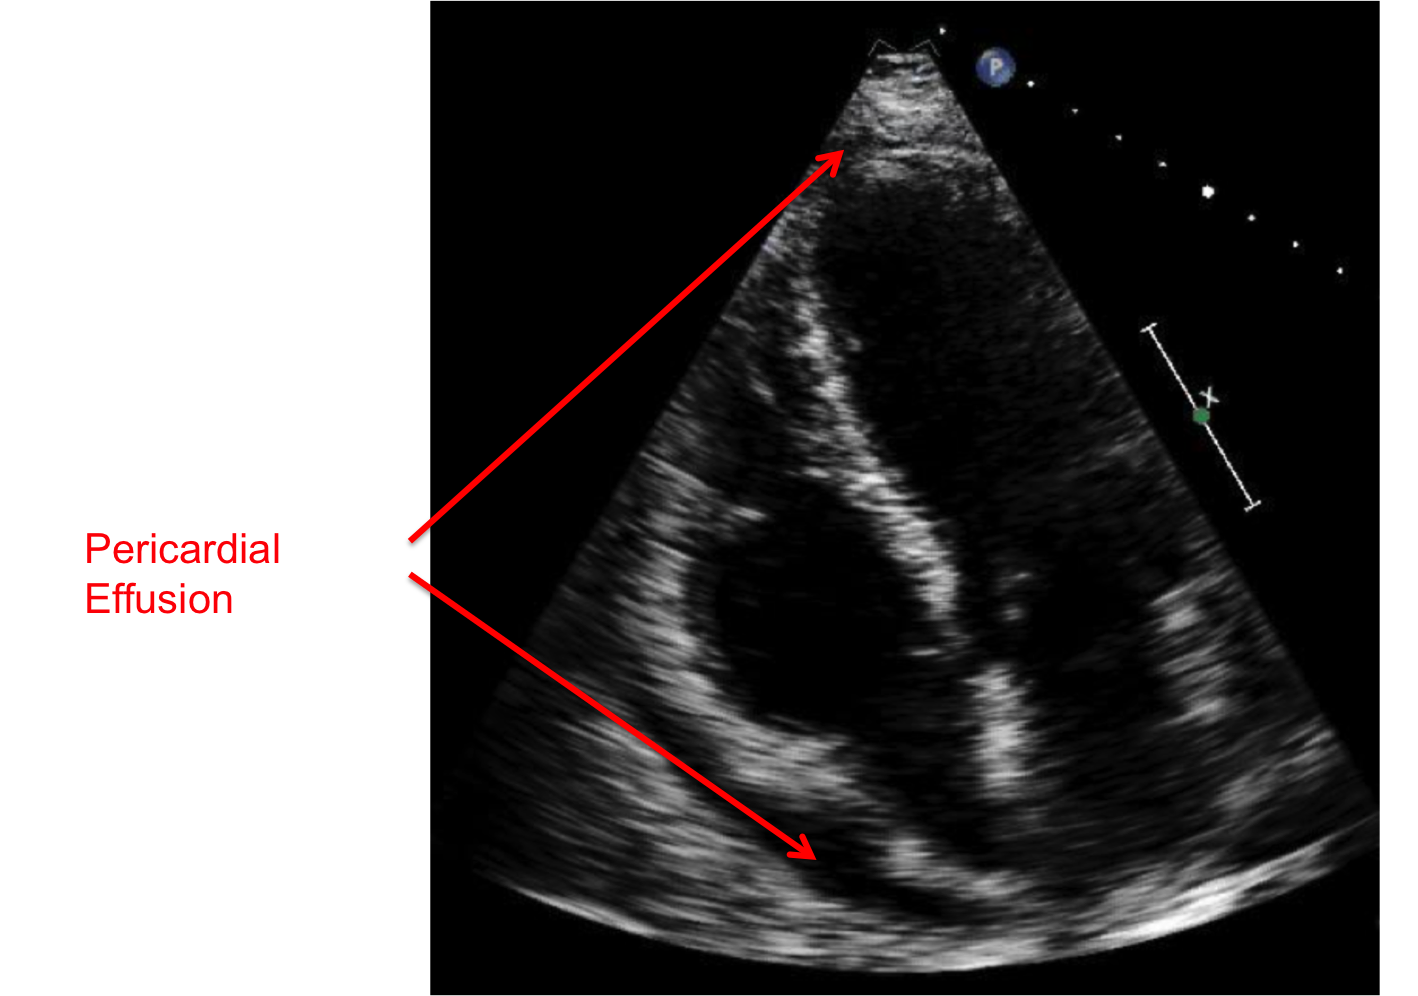

Treatment For Pericardial Fluid . learn how to identify and manage pericardial effusion, a condition where fluid accumulates in the sac around. pericardial effusion is the buildup of fluid around the heart, which can cause chest pain, shortness of breath and. pericardial effusion is a buildup of fluid in the pericardium, a fibrous sac that surrounds the heart, which can cause. once diagnosed, there are numerous treatment options available for the management of patients with pericardial. pericardial effusion is the buildup of excess fluid between the heart and the sac surrounding the heart. pericardial effusion is the buildup of too much fluid in the saclike structure around the heart. pericardial effusion is a buildup of fluid in the sac around your heart that can interfere with its function.